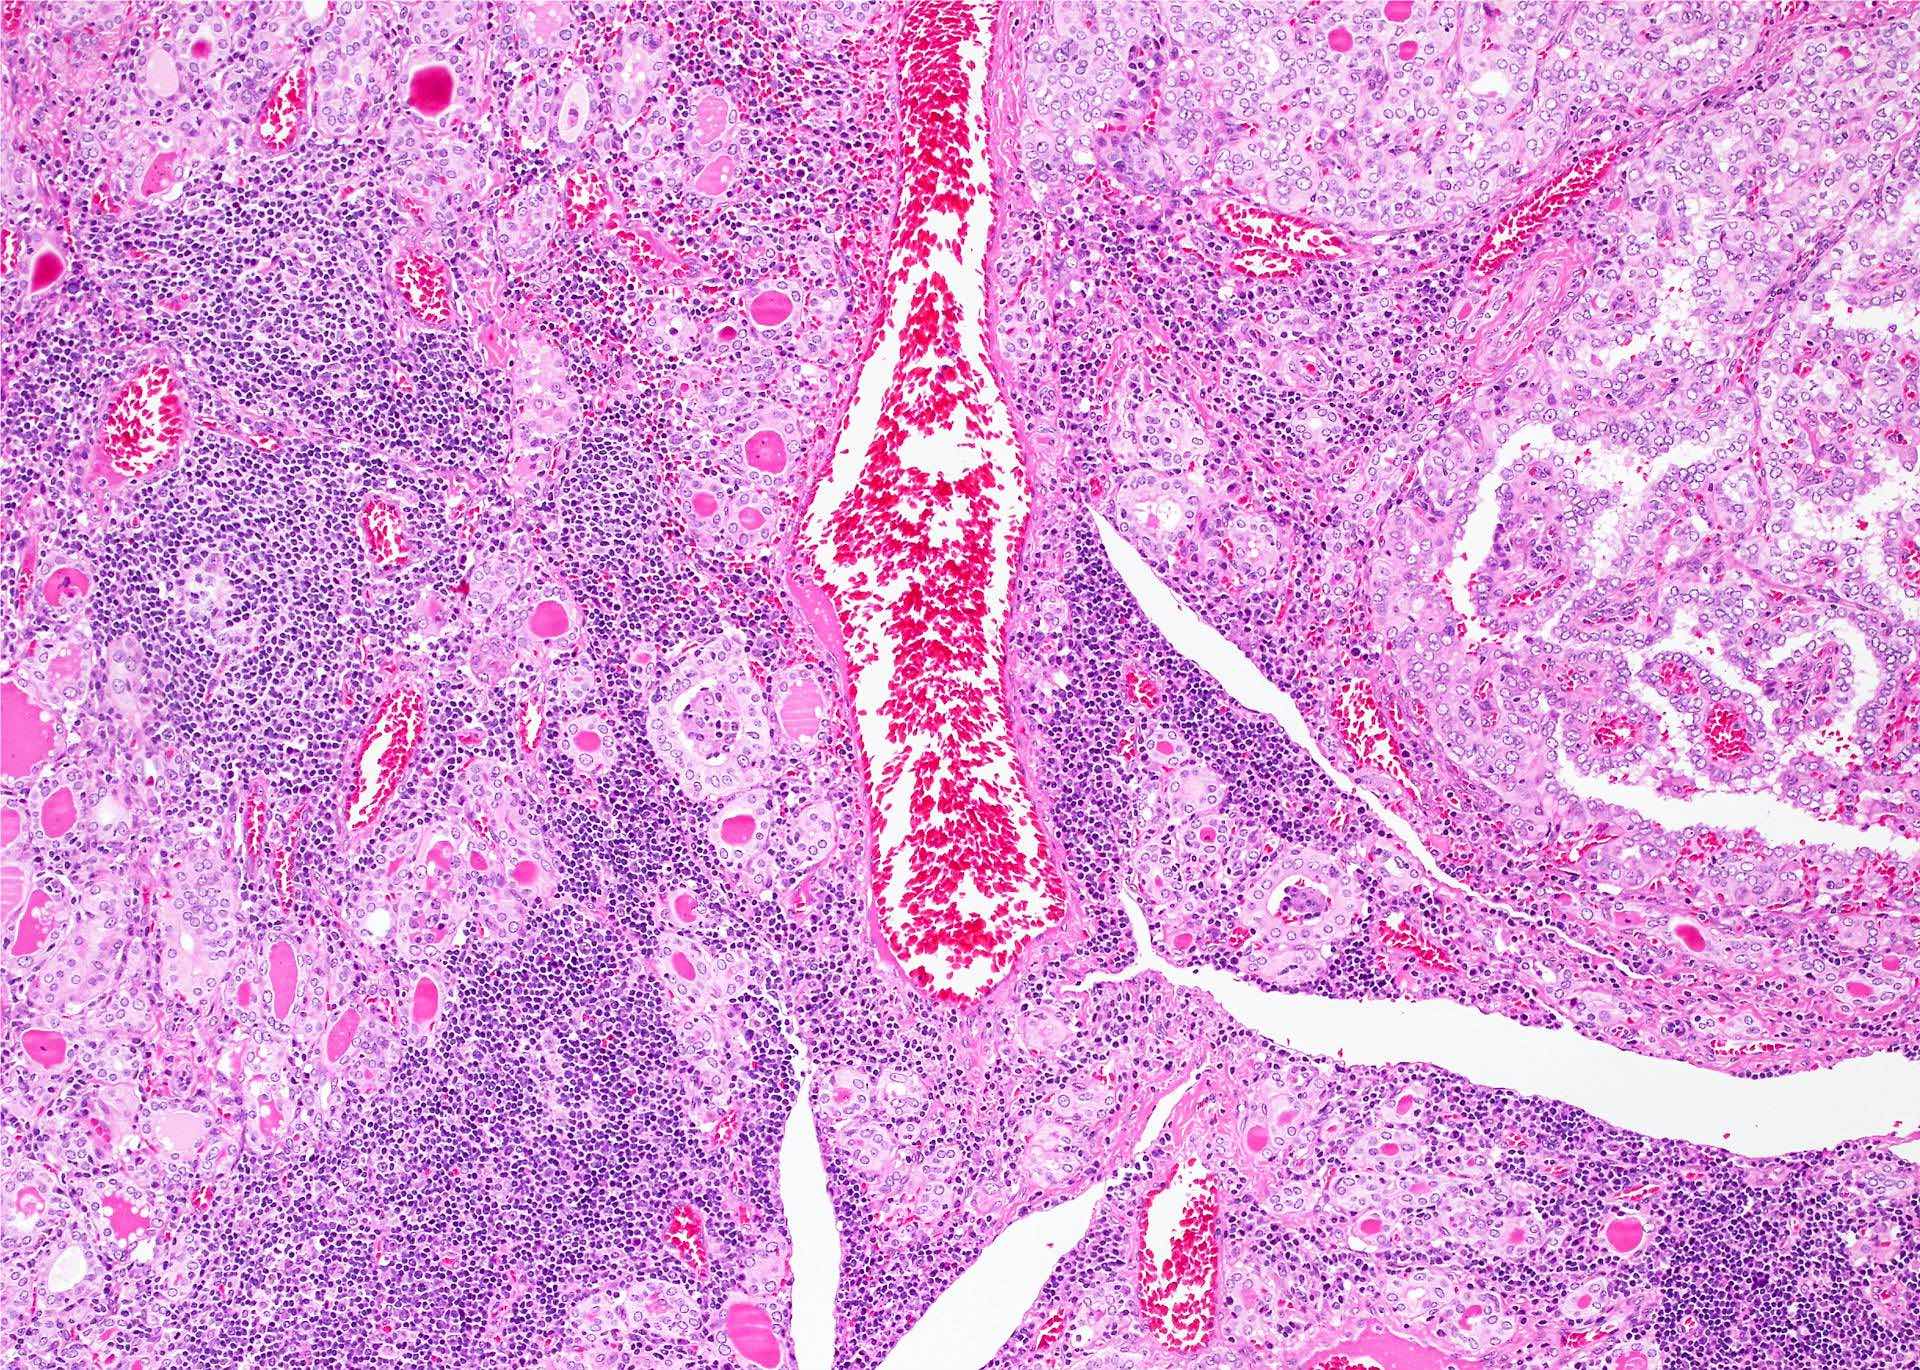

Histology Of Hashimoto’s Thyroiditis My Endo Consult Bromelain Hashimoto's Thyroiditis Hashimoto’s thyroiditis is also known as chronic lymphocytic thyroiditis or autoimmune. Hashimoto thyroiditis, also known as chronic autoimmune thyroiditis and chronic lymphocytic thyroiditis, is an autoimmune disease in which thyroid cells are destroyed via. Among these potential scenarios, the most common one constitutes autoimmune thyroiditis (hashimoto’s thyroiditis (ht), graves’ disease,. Hashimoto thyroiditis is an autoimmune disorder that presents with or. Bromelain Hashimoto's Thyroiditis.

Histology Of Hashimoto’s Thyroiditis My Endo Consult Bromelain Hashimoto's Thyroiditis Hashimoto’s thyroiditis is also known as chronic lymphocytic thyroiditis or autoimmune. Hashimoto thyroiditis, also known as chronic autoimmune thyroiditis and chronic lymphocytic thyroiditis, is an autoimmune disease in which thyroid cells are destroyed via. Using enzymes can help with overcoming symptoms of hashimoto’s including fatigue, hair loss, and infections as well as with reducing thyroid antibodies. Hashimoto thyroiditis is an. Bromelain Hashimoto's Thyroiditis.